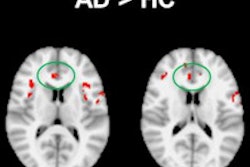

ASL images at baseline for patients with chronic low back pain showed a stronger connectivity between the medial prefrontal cortex of the brain and a network of brain areas known as the default mode network, compared with the healthy group.

Results also showed that the back pain patients experienced less pain when there was a greater connection between the default mode network and the medial prefrontal cortex, which, the authors noted, suggests that the connection may be a pain-protective mechanism.

In addition, the ASL images showed that the connectivity between the medial prefrontal cortex and the default mode network decreased after the assigned movements in back pain patients, but not in the control subjects.